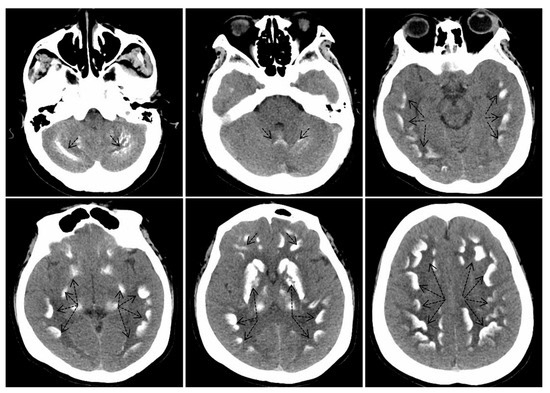

Американские исследователи выяснили, что соотношение мышц и скрытого жира на животе связано со старением мозга. Оказалось, что более…